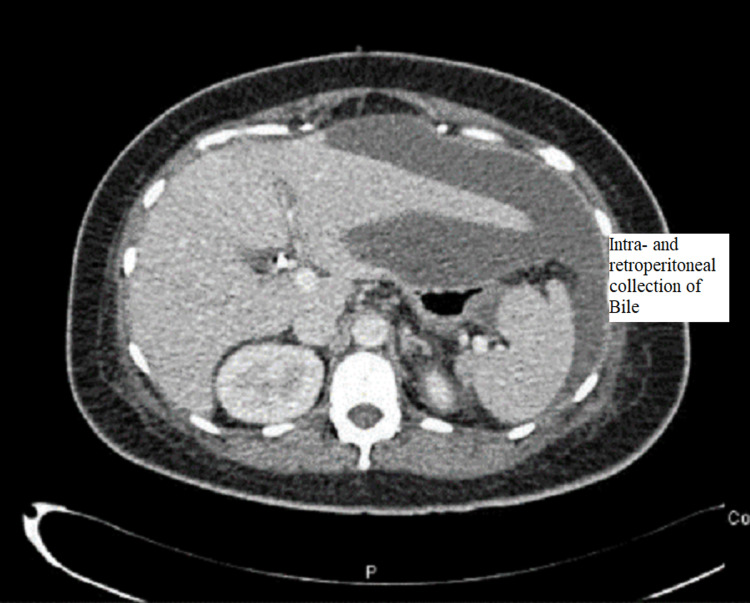

CT abdomen was done and showed a large amount of free fluid in the perihepatic, peri-splenic, and pelvic regions, along with extensive subcutaneous edema and stranding with free air within the right lateral abdominal wall (Figures 3–5). In addition, the CT revealed a mild intrahepatic biliary duct and CBD dilatation.

The patient was maintained on supportive treatment and close observation and was planned for endoscopic retrograde cholangiopancreatography (ERCP) and stenting. It showed a filling defect at the most distal part of CBD. Deep cannulation of CBD was achieved. A contrast leak was detected from the cystic stump with normal intra- and extrahepatic bile ducts. A partial sphincterotomy was performed, and a double pigtail stent was placed at the left hepatic duct, which eventually showed good contrast and bile drainage into the duodenum documented endoscopically and fluoroscopically (Figures 6, 7).